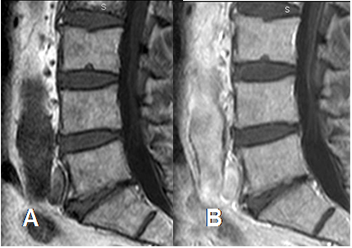

Fig 9. Medula ósea normal con contraste.

A: RM sagital en T1 en fase simple y B: RM en T1 luego de la administración de contraste, donde se aprecia aumento en la SI por el realce normal.